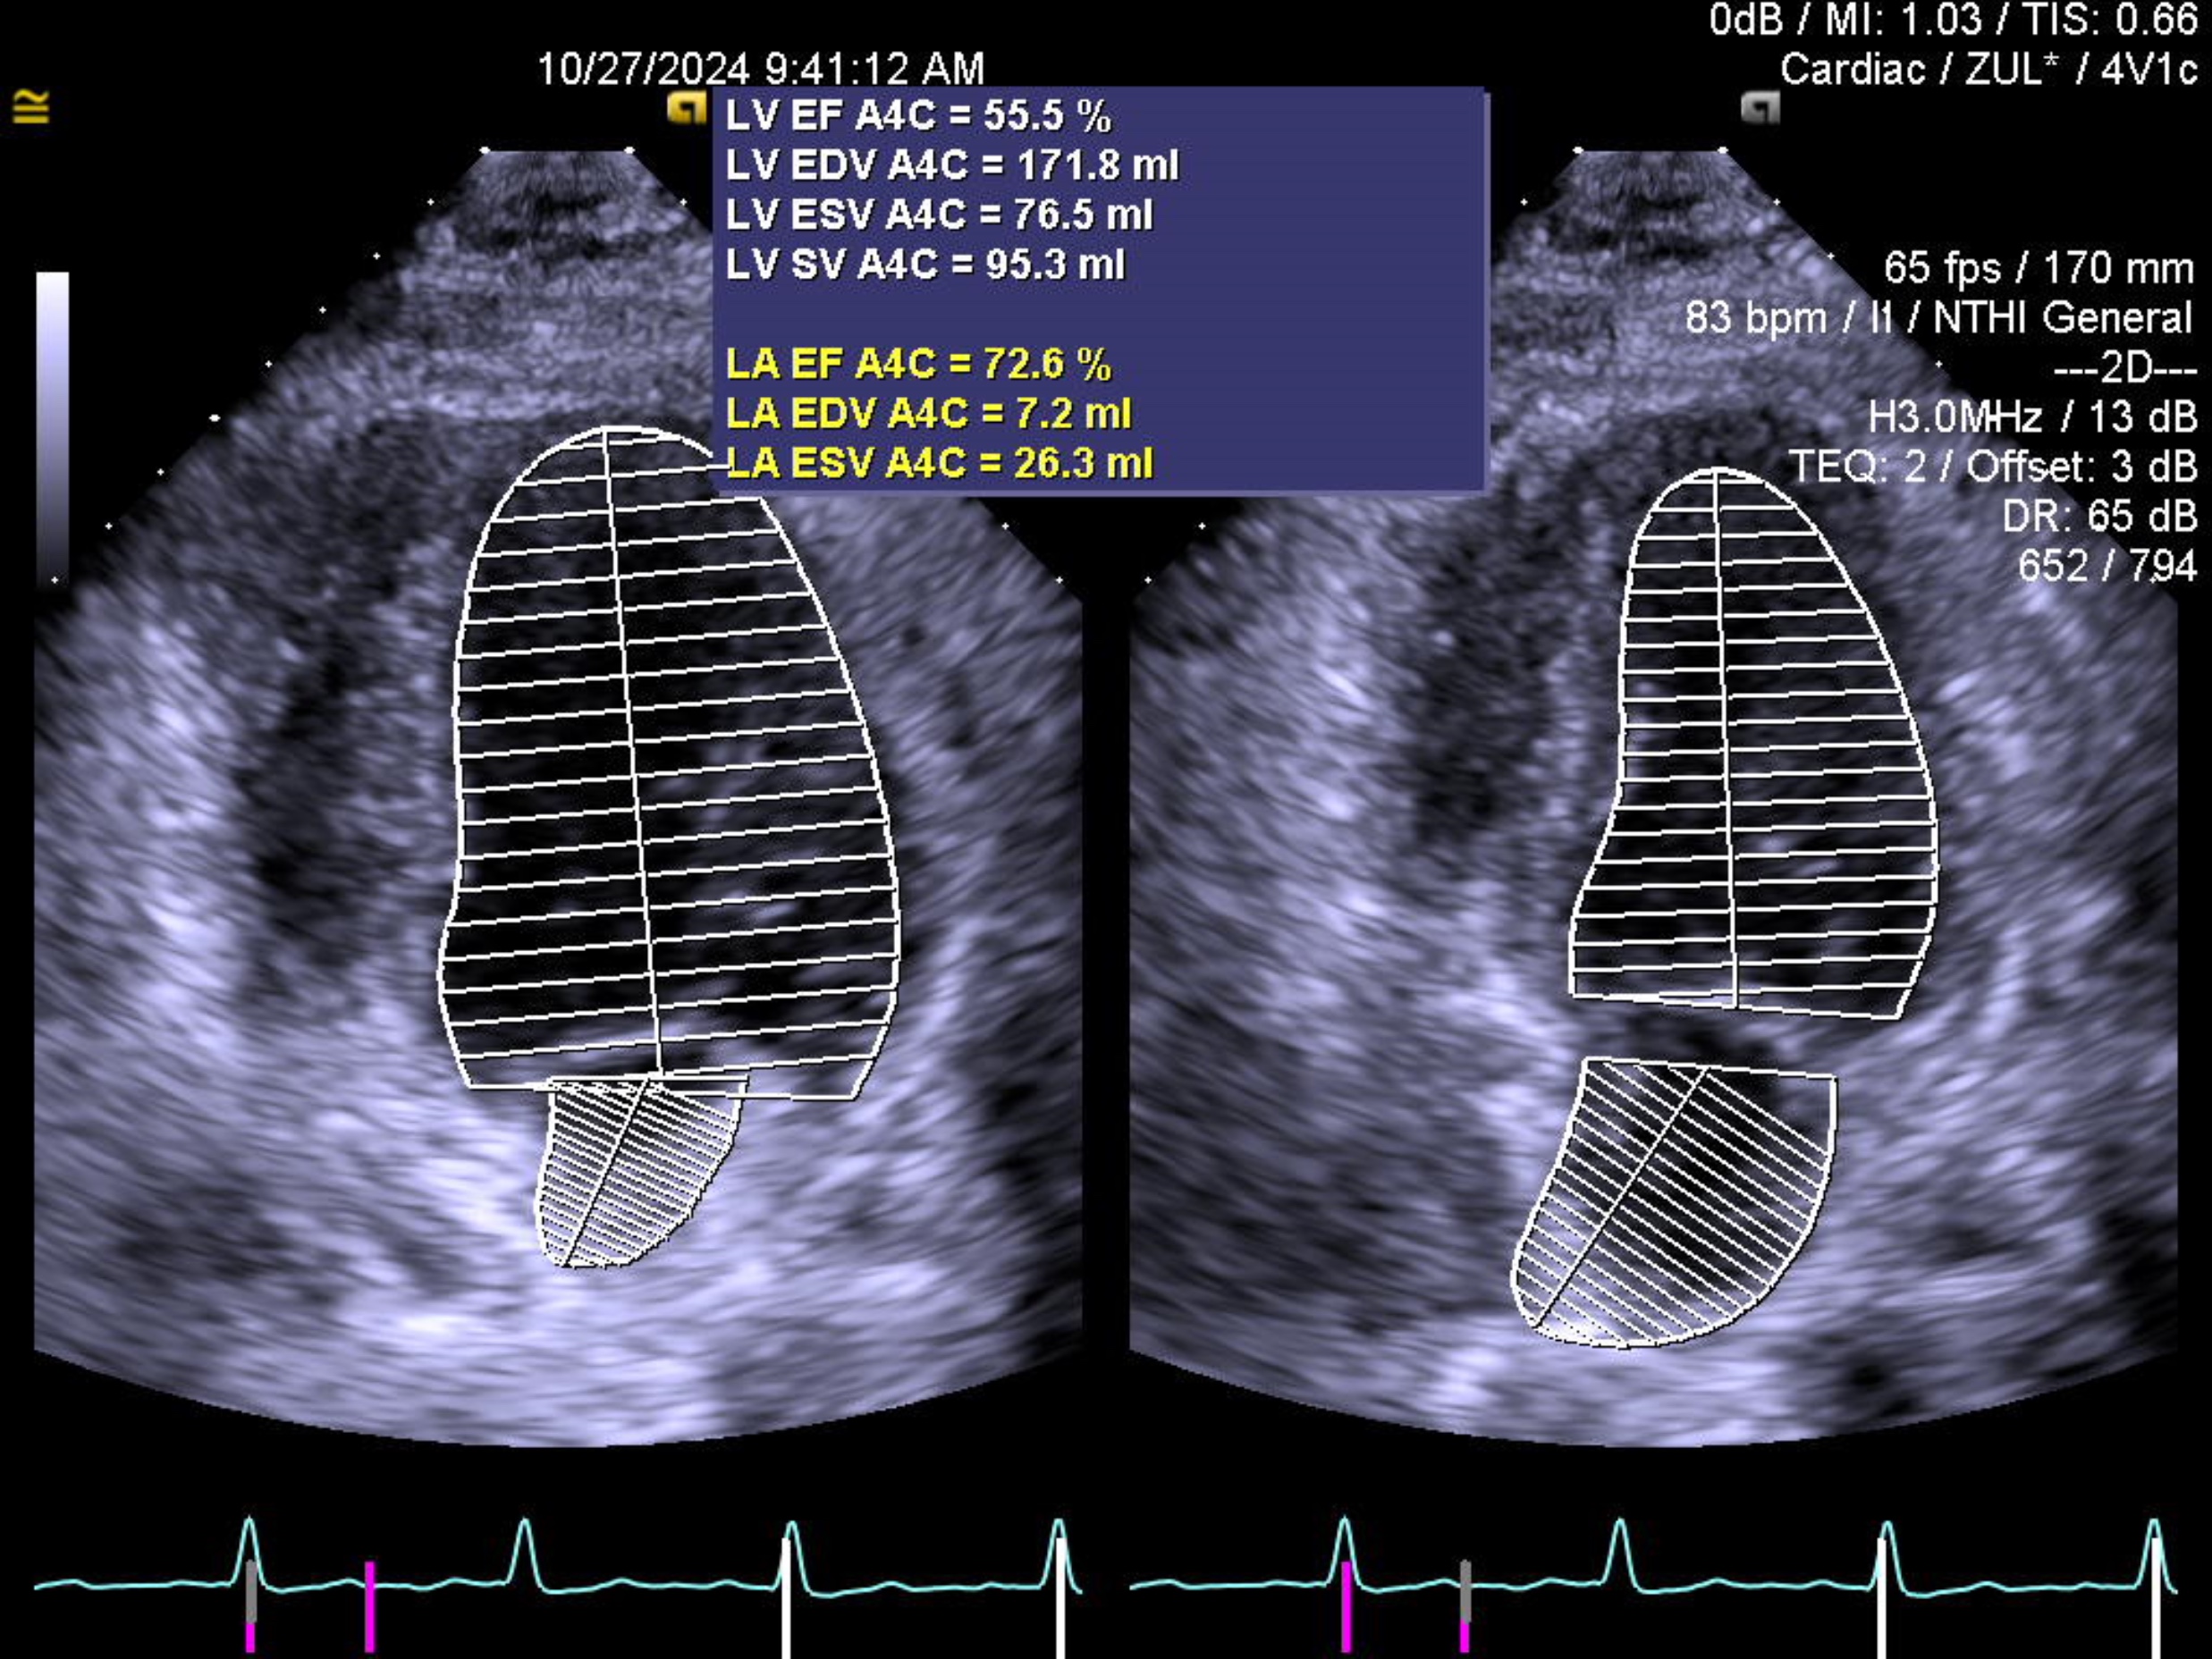

His blood investigations were unremarkable with a normal troponin reading. The electrocardiography shows sinus rhythm with normal axis, absence of left ventricular hypertrophy, Q wave, ST deviation or T wave inversion. The echocardiography showed no regional wall motion abnormality with normal left ventricular ejection fraction. A computed tomography of coronary artery revealed a subtotal occlusion over the left anterior descending artery (LAD).